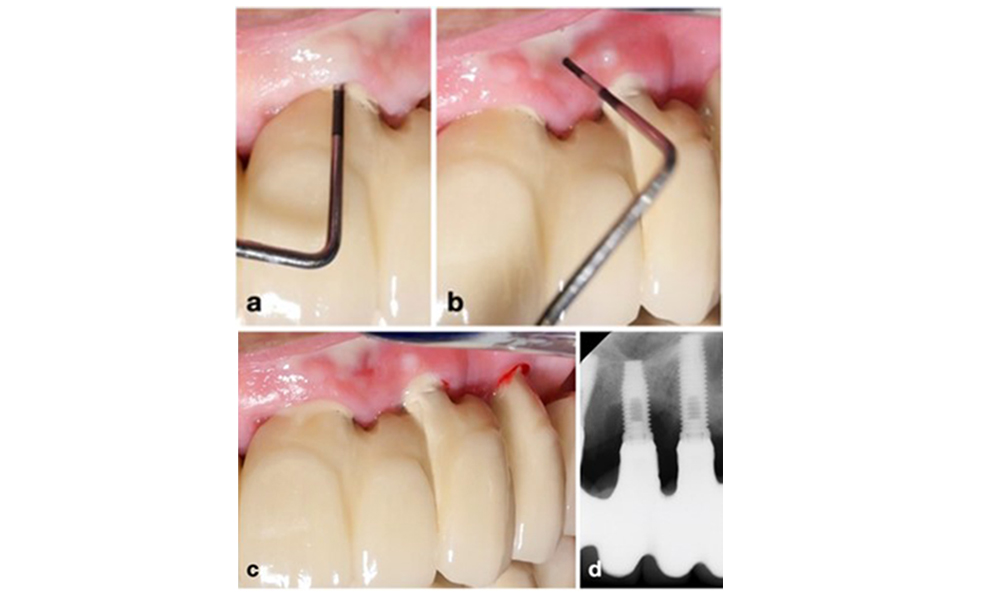

The World Workshop on the Classification of Periodontal and Peri‐Implant Diseases and Conditions from 2017 established diagnostic criteria for peri-implant mucositis and peri-implantitis (Renvert et al. 2018). Peri-implant mucositis is defined as (1) presence of inflammation around the implant (i.e., redness, swelling, line or drop of bleeding within 30 seconds of probing), combined with (2) no additional bone loss after initial healing (figure 1).

Peri-implantitis is identified by (1) signs of inflammation similar to mucositis, (2) radiographic evidence of bone loss after initial healing and (3) an increase in probing depth compared to measurements taken shortly after placing the prosthetic reconstruction (figure 2). In the absence of previous radiographs, radiographic bone level of ≥ 3 mm along with bleeding on probing and probing depths ≥ 6 mm, indicates peri‐implantitis.